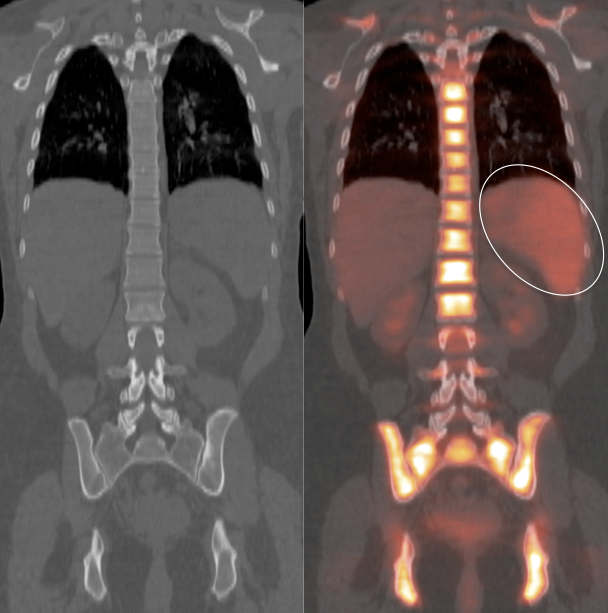

- Therapy-Induced Splenic Activation